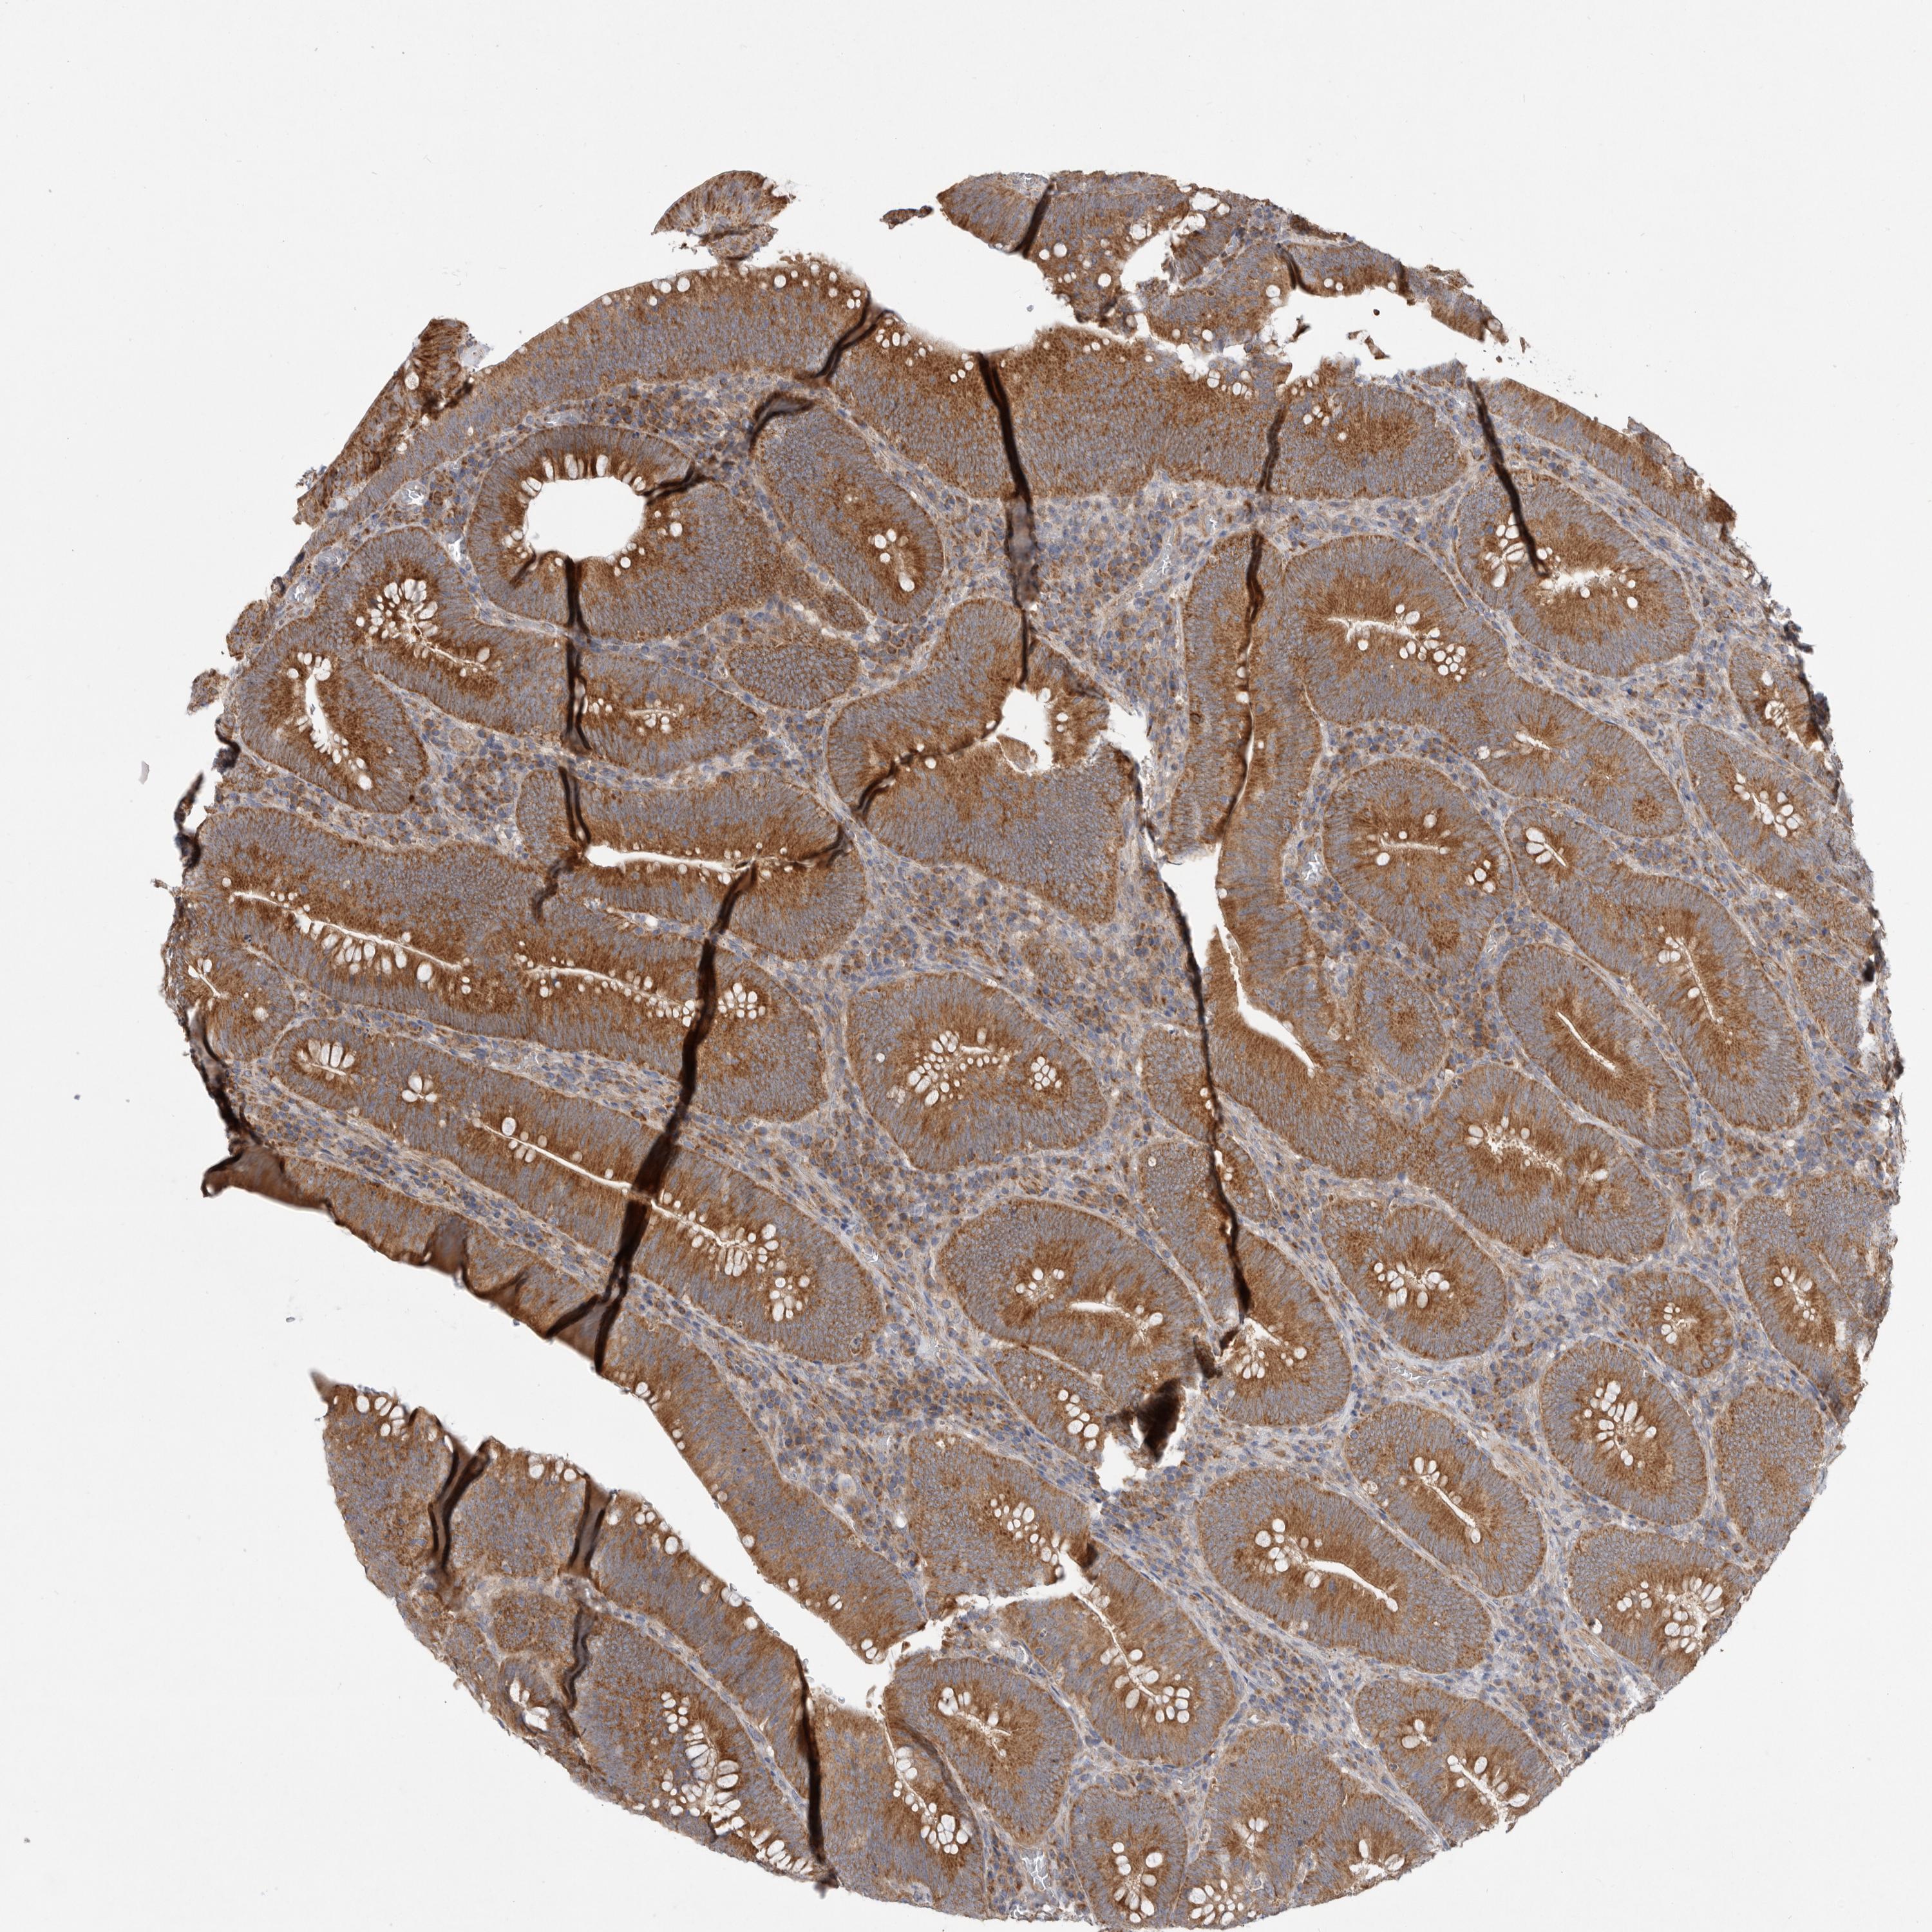

CANCER COLORECTAL CANCER Show tissue menu

Colorectal cancer

Human cancer

Colon adenocarcinoma